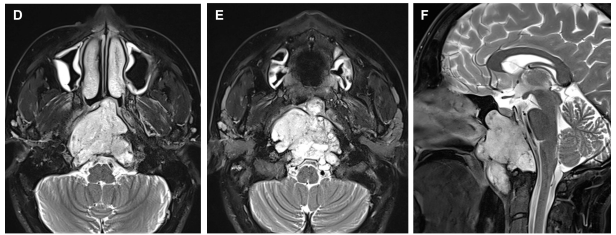

一名11岁男孩因梗阻性脑积水出现头痛和复视。脑部MRI显示四叠体板处有一个脑内部分对比增强的病变,从小脑延伸至松果体,并导致脑积水。对病变进行了次全切除,男孩被确诊为间变性神经节细...